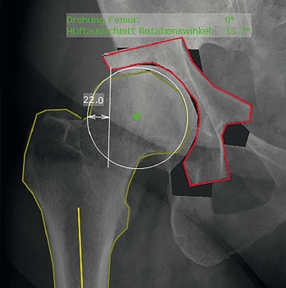

Chức năng “Triple pelvic osteotomy” trong mediCAD® cung cấp một tùy chọn dễ sử dụng cho việc lập kế hoạch đặt lại khớp háng trong các trường hợp thiểu sản khớp.

Chức năng này giúp bác sỹ có thể tính toán mức độ xoay và độ bù của mảnh cắt xương chỉ với một vài cú nhấp chuột

Sau đó, phần mái của ổ cối mới cũng được tính toán